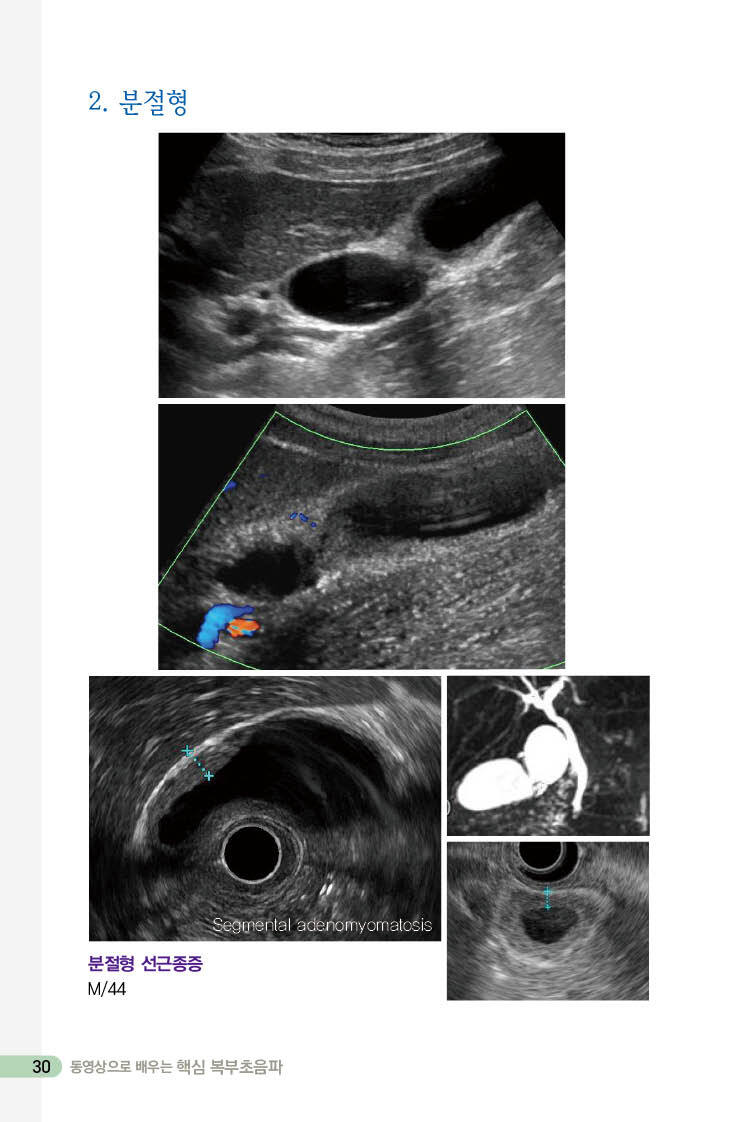

2. 분절형 30